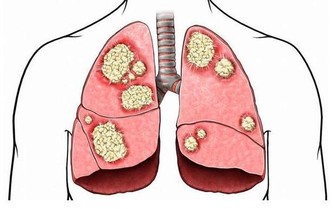

引起的眼部變化主要是眼底血管的改變,表現為眼底微血管變細、扭曲、滲出,甚至血管破裂、出血,會造成患者視力下降或突發性看不見東西。主要防治辦法就是控制血壓、血脂。所以,中老年人的飲食,應貫徹低脂、低鹽、低糖的原則,重視對動脈硬化和高血壓的防治。檢查身體時不要忘記檢查眼底。 外傷感染 雙眼角膜因為在眼球表面,所以最怕外傷和病毒、細菌感染。人們常說“眼睛裡揉不得沙子”,說的就是角膜容不得半點灰塵等異物。特別是人到老年,眼淚減少,角膜乾燥,角膜更易受到損傷。所以,平時要加強對角膜的保健和防護,避免灰塵異物損傷,避免強光照射,重視衛生,不要用臟手亂揉眼睛,平時宜少吃辛辣刺激性食品,少飲酒。此外,防止眼外傷、及時補充飲水等,對保護雙眼的健康都很重要。 屈光不正 在靜止狀態下,平行光線經眼屈光系統的折射後聚焦於視網膜上,這便是正視眼。若平行光線經眼屈光系統的折射後不能聚焦於視網膜上,這是非正視眼,稱為“屈光不正”。屈光不正包括近視、遠視及散光。特別是患高度近視而沒有得到及時矯正,最易導致“視網膜脫離”(就是視網膜感光層與其下層組織之間的分離),是引發失明的重要原因。 顱內壓增高 無論是顱腦外傷、炎症或腫瘤,只要引起顱內壓力增高,就會影響眼靜脈的回流,出現視乳頭水腫,損害視神經,嚴重者可導致失明。顱內腫瘤還會直接壓迫視神經或損壞視中樞而造成視野缺損或導致不同程度的非眼病性致盲。所以,一定要加強預防顱腦外傷,重視對腦部炎症和腫瘤的防治。 青光眼 眼壓是眼球內容物(房水、晶狀體和玻璃體)對眼球壁施加的壓力。一旦房水循環阻塞、眼壓升高,就會患青光眼。此病若沒有得到及時診斷和治療,患者可能會在數天,甚至數小時內失明。急性閉角型青光眼可雙眼先後發病,也可同時發病。世界上約有五分之一的眼盲為青光眼所致。平時體檢不要忘了測眼壓,一旦發現眼壓升高或發現青光眼的症狀,一定要立即求診,唯有及時手術才能保住視力。  老花眼